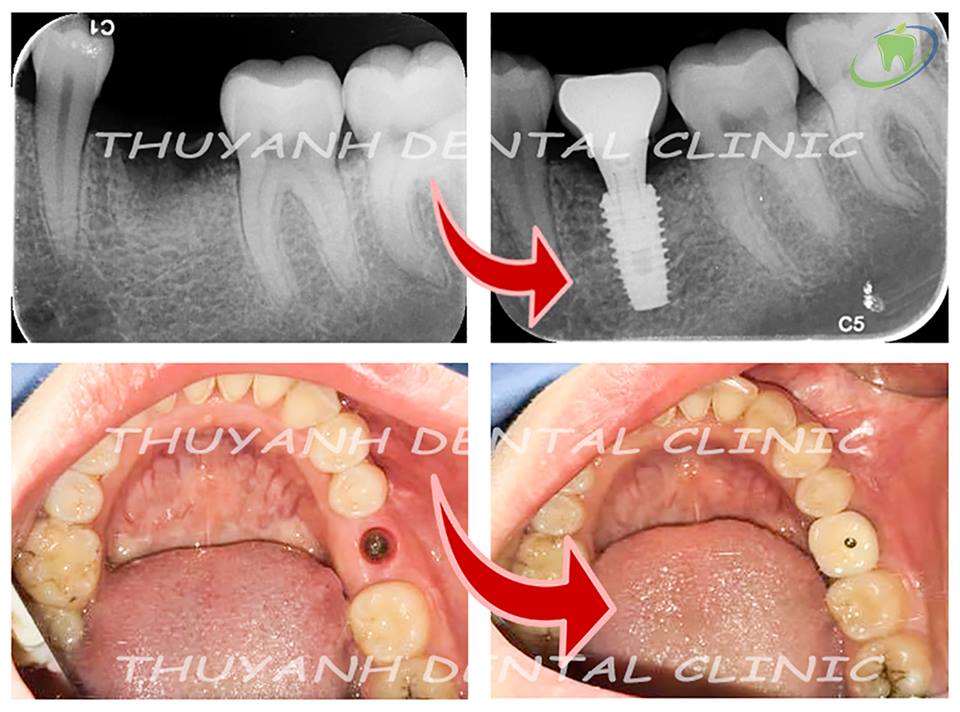

Tiểu phẫu thuật cấy ghép Implant có tốn thời gian và phức tạp ???. Thực tế không phải như vậy. Việc phẫu thuật cấy ghép Implant chỉ mất khoảng 20 phút cho 1 răng implant, tương đương thời gian nhổ một chiếc răng thường. Vì bạn đặt hẹn trước, phòng tiểu phẫu sẽ được chuẩn bị sẵn sàng để bạn cảm thấy thoải mái và tiết kiệm thời gian của bạn.

Cấy ghép Implant có đau không ??? Sau khi ghép Implant, bạn vẫn có thể làm việc bình thường, hoặc chỉ cần 1 ngày nghỉ. Tuy nhiên, nếu bạn cần phải làm nhiều thủ thuật, như nhổ răng đồng thời cấy ghép Implant cho nhiều răng, hay phải ghép xương tự thân, nâng xoang hở, thì bạn sẽ cần nhiều thời gian để nghỉ ngơi hơn, khoảng 3-7 ngày tùy trường hợp, và bác sĩ cũng sẽ thảo luận kỹ khi bạn đến tư vấn, để bạn có thể sắp xếp thời gian cho công việc, hay chuyến du lịch của bạn.

Phục hình răng cấy ghép Implant trong thời gian lành thương:

Hàm răng có bị trống trong quá trình cấy ghép Implant ??? Bạn cảm thấy lo ngại rằng mình phải để trống răng trong suốt thời gian chờ lành thương và Implant tích hợp xương ? Bác sĩ tại Nha khoa Thùy Anh sẽ luôn chuẩn bị sẵn răng tạm sau khi cấy ghép Implant cho bạn.

Răng tạm thông thường không dùng để nhai được mà chủ yếu là để thẩm mỹ. Bạn có thể giao tiếp, làm việc được tốt với răng tạm (thông thường là hàm tháo lắp), nhưng để ăn nhai ngon lành, bạn phải đợi một khoảng thời gian tích hợp xương của Implant, rồi bác sĩ làm răng sứ trên Implant, thì khi đó kết quả cuối cùng sẽ làm bạn hài lòng.

Phục hình răng sứ trên chân răng Implant:

Công việc phục hình răng trên chân răng Implant tương tự như khi bạn đi làm mão răng, hay cầu răngthông thường

Cấy implant thay thế 1 răng hàm bị mất do sâu răng cho bạn khách hàng nữ